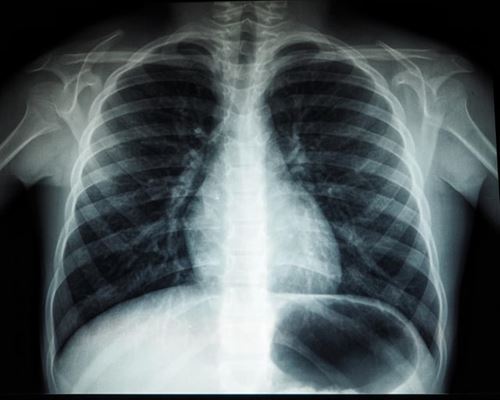

Røntgenteknologi – Det bruges den til i dag

Du har sikkert hørt om røntgenbilleder og røntgenfotografering før. Det er absolut intet nyt. Røntgenstråling blev opdaget helt tilbage i 1895 af fysikeren Wilhelm Conrad Röntgen, som faktisk opdagede